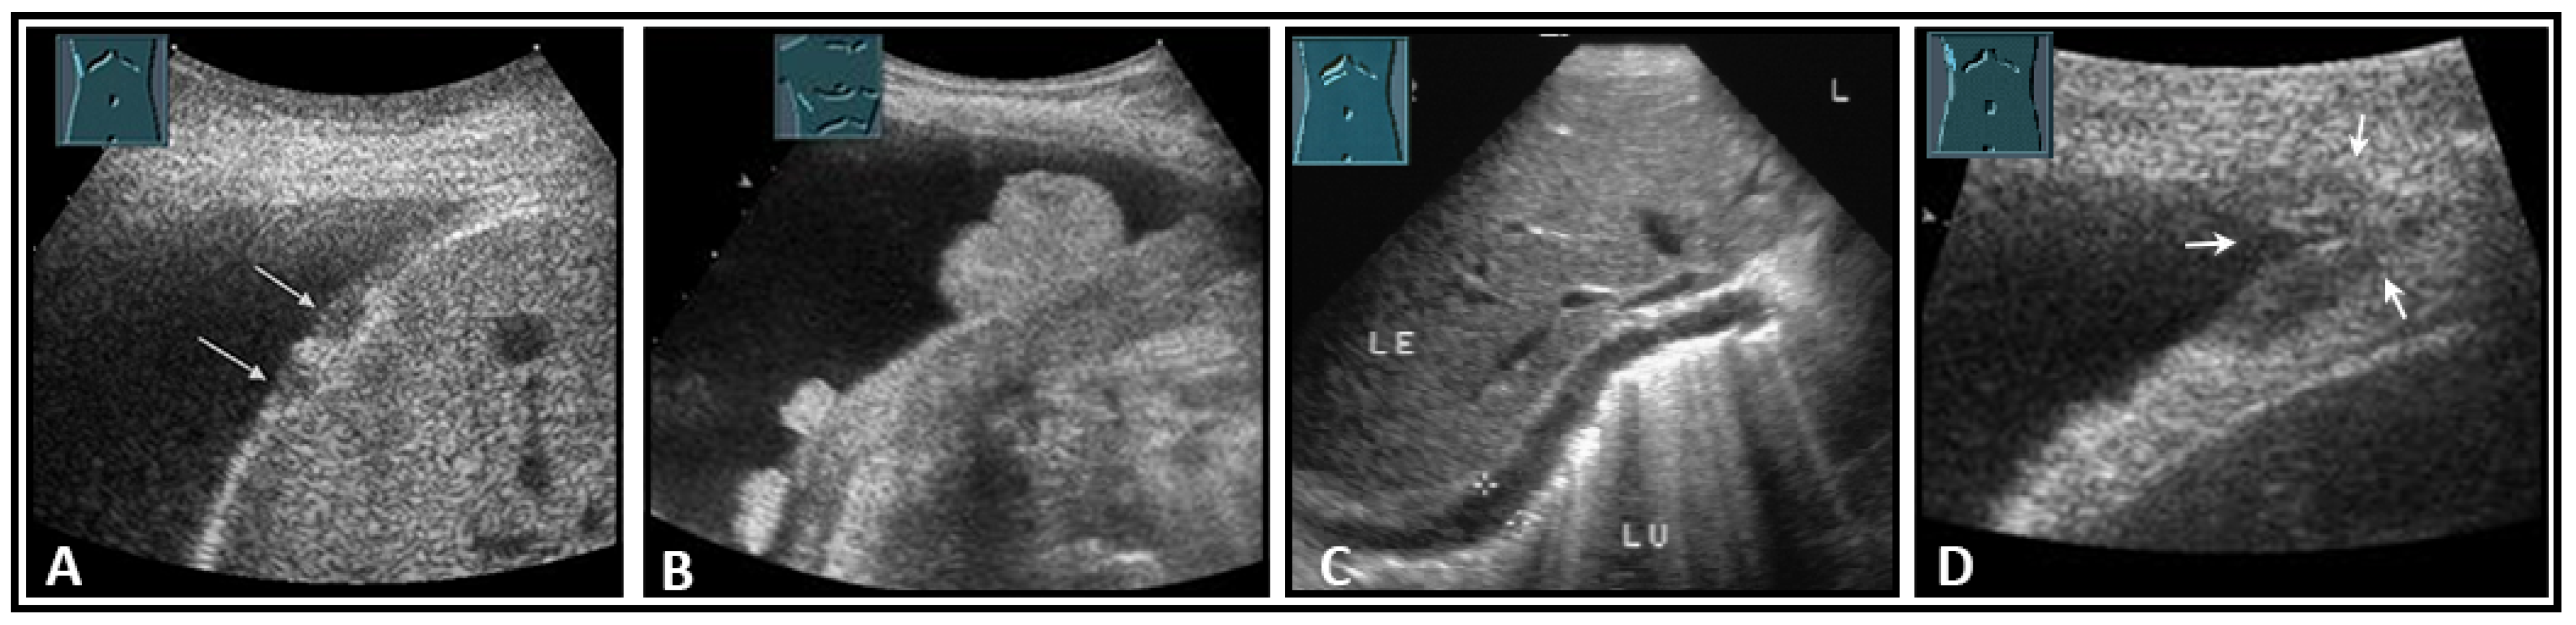

Figure 29.

Visualization of the right-sided (A) and left-sided diaphragm (B) with the lateral intercostal view and of the right-sided diaphragm with the subcostal view (C).

Border shadow artifacts may indicate an apparent diaphragmatic gap, which disappears when the transducer position is changed (Figure 30).

Figure 30.

Illustration of artifact-related apparent diaphragmatic rupture (A, arrow) with regular findings and slightly lateral sound propagation to the diaphragm (B).